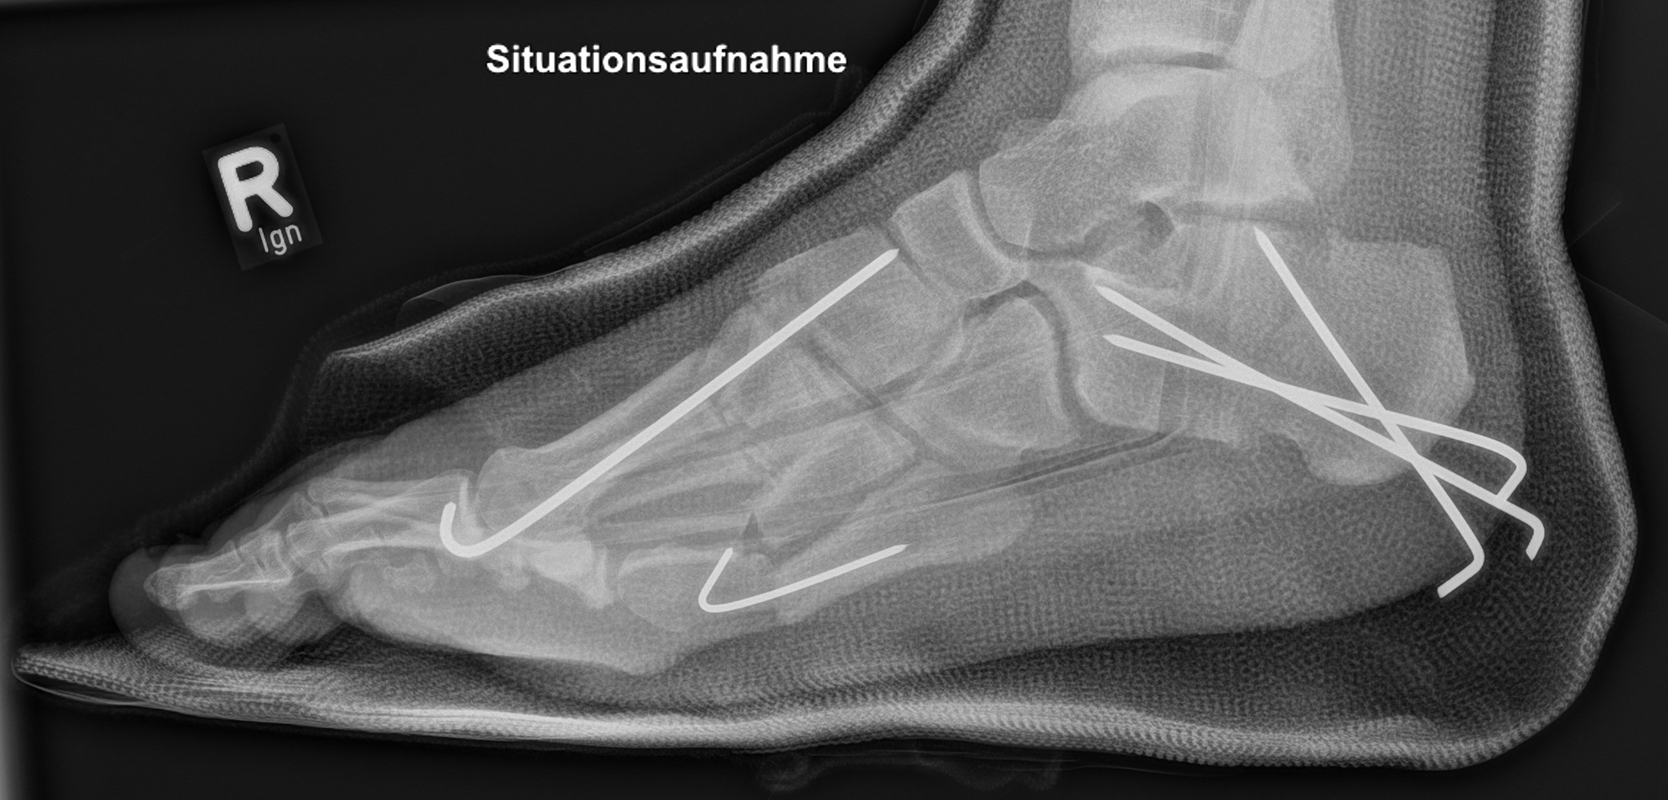

Calcaneus-Osteotomie

Die minimalinvasive Calcaneusverschiebeosteotomie bietet eindeutige Vorteile gegenüber dem offenen Verfahren, sodass wir bei Kindern und Jugendlichen nahezu keine offene Verschiebeosteotomie mehr durchführen. Am Calcaneus liegt die offene Wachstumsfuge dorsal. Bei der Durchführung müssen Schenkel der V-förmigen Osteotomie daher etwas steiler angelegt werden, in einem stumpfen Winkel (siehe Abb. 3 a-j). Für die Osteotomie liegen unsere Patienten auf dem Rücken und der BV wird für die exakte Seitaufnahme eingestellt. Der Fuß lagert auf einem hohen OP-Kissen und die Osteotomie kann bequem mit einem langen Kirschner-Draht und einem sterilen Stift angezeichnet werden (Abb. 15).

Damit lässt sich im Verlauf Röntgenstrahlung für die jungen Patienten vermeiden und die minimalinvasive Osteotomie kann sicher durchgeführt werden. Anschließend erfolgt die Verschiebung oder Impaktion. Ist ein Gleiten nach plantar oder cranial des distalen Fragmentes erwünscht, wird die Osteotomie schräg ohne V-Form entweder verlängernd oder verkürzend durchgeführt (Abb. 16).

Durch den knöchernen Defekt der Fräse gelingt die Verschiebung bei der minimalinvasiven Osteotomie im Fall von strukturell festen Klumpfüßen mit starkem Zug der verkürzten Achillessehne oder bei einer fixierenden spastischen Grunderkrankung einfacher gegenüber dem offen Verfahren. Ein weiteres Plus bei hyperaktiven Weichteilen ist die Vermeidung der ungewollten Cranialisierung des dorsalen Fragmentes durch die V-förmige Osteotomie (Abb. 16).

Die minimalinvasive Calcaneusverschiebeosoteotomie kommt somit in der Versorgung von kindlichen und jugendlichen Fußdeformitäten in einem weiten Erkrankungsspektrum zum Einsatz (Abb. 16):

- Plattfuß – Varisation

- Klumpfuß residual – Valgisation und ggfs. Cranialisation sowie Impaktion

- Klumpfuß überkorrigiert – Varisation und ggfs. Plantarisierung

- Hohlfuß – Cranialisation und ggf. Valgisation (alternativ minimalinvasive Austin-Osteotomie)

Abb. 16 a-f: Varisation einer valgischen Calcaneusstellung bei Knick-Senk-Fuß mit V-förmiger Osteotomie axiale Ansicht (a), seitliche Ansicht (b), d. p. Ansicht (c) und nach Entfernung der Drähte seitliche Ansicht (d), Caudalisierung des dorsalen Calcaneus bei iatrogenem Plattfuß nach Klumpfußüberkorrektur (e) und Cranialisierung beim Hohlfuß (f).